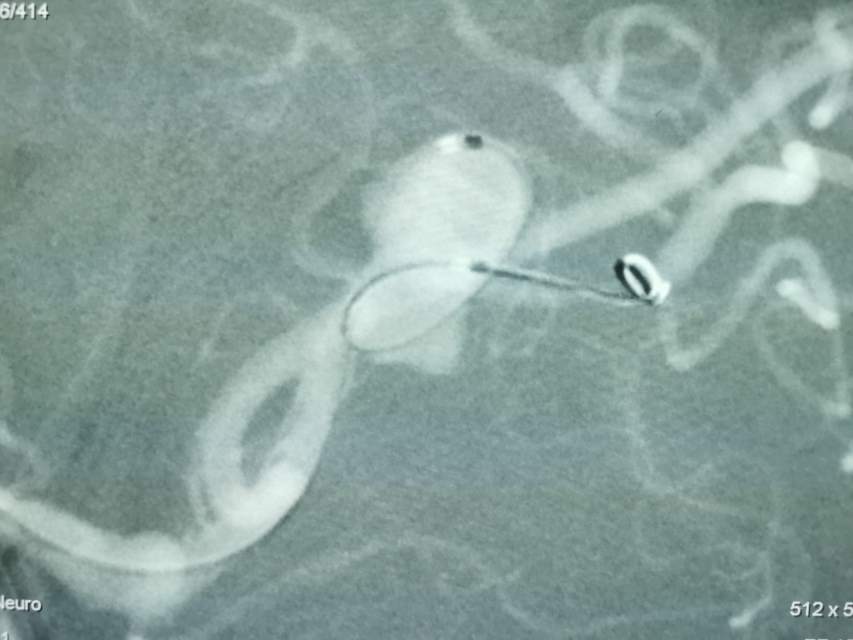

福建中年女性,近期在外查出“颅内动脉瘤”,经推荐转来我院诊治。患者的颈内动脉通路迂曲,动脉瘤也位置奇特,解剖复杂,动脉瘤远近段的血管弯弯绕绕,重重叠叠,眼花缭乱,难以兼顾找到最佳位置。最终克服困难,将“基底型”动脉瘤改变为“侧壁型”动脉瘤,顺利给予治疗……